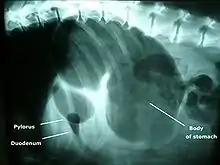

X-ray from the underside of a dog with GDV. The dark area is the buildup of gas.

A diagnosis of GDV is made by several factors. The breed and history often gives a significant suspicion of the condition, and a physical examination often reveals the telltale sign of a distended abdomen with abdominal tympany. Shock is diagnosed by the presence of pale mucous membranes with poor capillary refill, increased heart rate, and poor pulse quality. Radiographs (X-rays), usually taken after decompression of the stomach if the dog is unstable, shows a stomach distended with gas. The pylorus, which normally is ventral and to the right of the body of the stomach, is cranial to the body of the stomach and left of the midline, often separated on the X-ray by soft tissue and giving the appearance of a separate gas-filled pocket (double-bubble sign).[4]